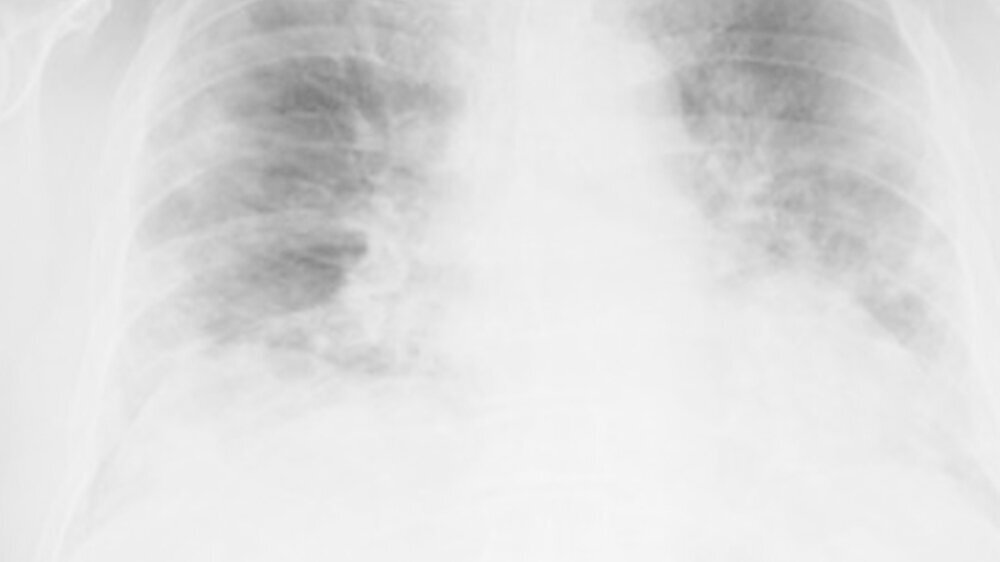

+++ Gerüchte um alternative Gegenmittel kosten Leben +++ New Yorks U-Bahn bittet Apple um Alternative zu Face ID +++ Nasenspray soll vor COVID-19 schützen +++ So schnell sitzt die OP-Maske besser +++ Studentin entwickelt Röntgensoftware für Früherkennung +++

Das neu identifizierte Coronavirus SARS-CoV-2 verursacht die "Corona virus disease 2019" (Covid-19) und ist Auslöser der COVID-19-Pandemie.